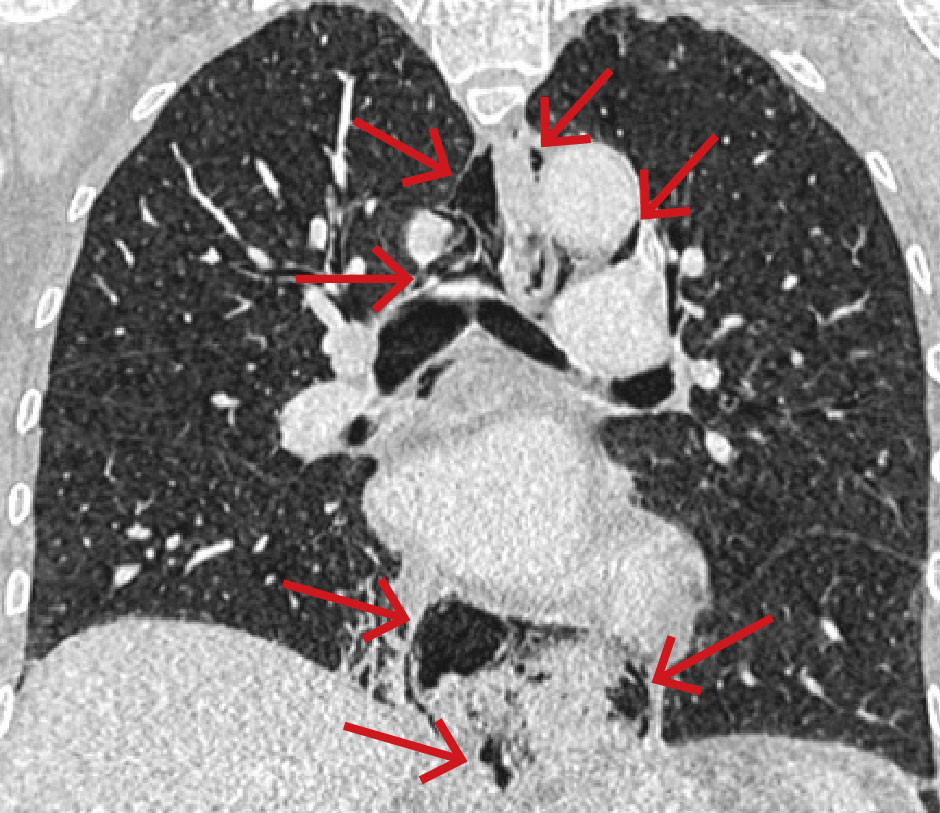

På grunn av uavklarte smerter ble kvinnen undersøkt med CT toraks, abdomen og bekken med intravenøs kontrast. Undersøkelsen viste spredte små luftlokulamenter i bløtdeler på hals, i mediastinum, langs øsofagus og i øvre abdomen i tilslutning til cardia ventriculi (figur 1). Hun hadde også beskjedne mengder pleuravæske bilateralt og beskjedne fortetninger deklivt i høyre underlapp.